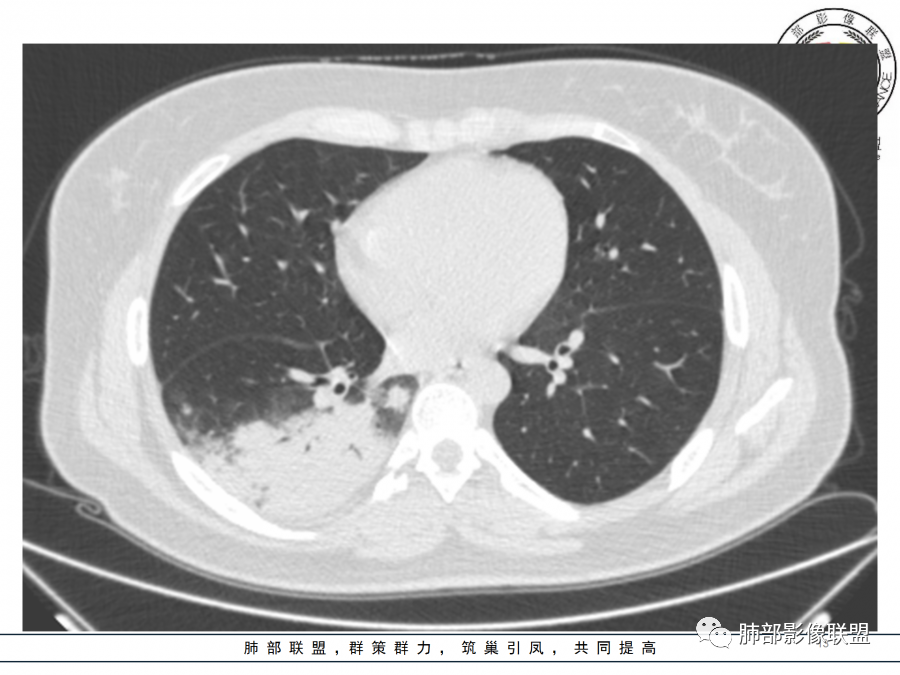

26岁,女性,发热、咳嗽5天。咳少量黄痰,起病急,病程短,白细胞及中性高,血沉及D-二聚体增高。胸部CT:右肺下叶大片实变,长轴沿胸膜分布,宽基底与胸膜接触,边界不清,周围GGO,部分团片影融合,病灶内可见支气管充气征,部分支气管进入病灶后阻塞。考虑:感染性病变,隐球菌?脓毒肺栓塞?鉴别:肺炎型肺Ca。

年轻女性,右肺下叶一大片实变影,似有多个结节影融合,周围有晕,内见支气管充气征,部分支气管进入后截断,病变近胸膜,长轴胸膜平行,考虑炎性,隐球菌首先考虑。

青年女性,影像表现右肺下叶胸膜下大片状实变影,近端见充气支气管征,边缘见片状磨玻璃影,下叶背段尚可见一结节。考虑感染性病变,隐球菌感染可能。

右下肺大片实变影,空气支气管征,边缘GGO,小叶间隔增厚,周围有蘑菇兄弟,基底宽,与胸膜平行,考虑隐球菌感染,鉴别肺炎型肺癌。

晨读:年轻女性,右肺胸膜下实变影,平行于胸膜,边缘磨玻璃影,内见支气管充气征,走形自然,略扩张。考虑感染性改变,隐球,肺链。2月发病,病毒性肺炎要考虑。鉴别淋巴瘤。

晨读:年轻女性,发热咳嗽5天。白细胞计数升高。右肺下叶大片状高密度影,边缘模糊,有实变 GGO,其内见支气管气相、无受压变细,无枯枝表现,其近端支气管无异常,右肺下叶背段见结节状影,定性考虑:炎症,隐球菌感染可能,炎症型肺癌不支持。

右下肺胸膜下大片状高密度影,其长轴与胸膜平行,病灶近端GGO模糊,部分支气管进入后阻断,支持感染性病变,考虑隐球菌

细菌性肺炎是沿着支气管往周围肺泡散开,内朝外,沿着叶段分布,受到支气管管辖,呈扇形,与支气管长轴平行,与胸膜垂直,隐球菌就是外朝内,外就是肺小叶内的肺泡,外周的。

肺小叶。他就是一个个肺小叶的融合,胸膜平行,和病毒一样。只是病毒在间质,是肺小叶分布的毛玻璃。隐球菌是肺实质,肺泡,肺小叶的实变。

这个病变也不是一个起源中心,胸膜下,多发结节状、实变影。而大叶性肺炎多数由内-外大片状。所以是肺实质多发融合病变。单纯从影像上,还是比较符合隐球菌特点,胸膜下,多发、多中心,相互融合(兄弟齐心)。